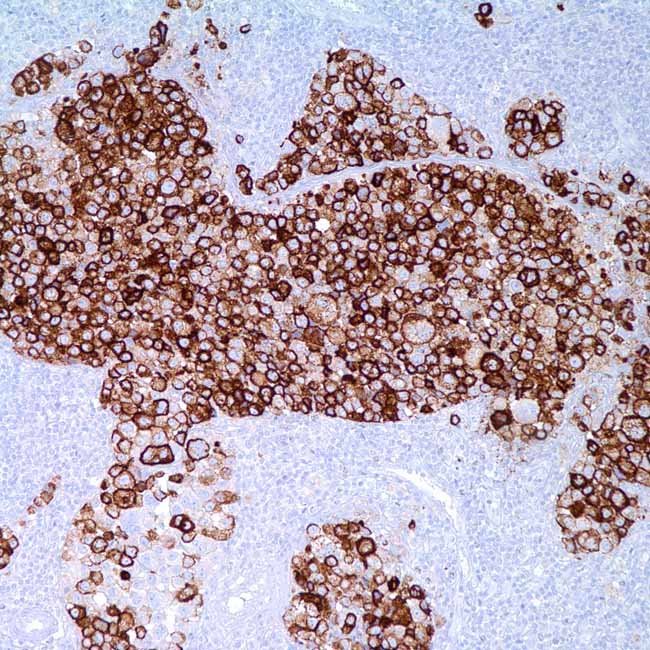

HMB-45 (HMB-45)

HMB45 is a widely recognized monoclonal antibody usedto detect a specific melanosomal glycoprotein. It is highlyreactive with a range of melanocytic lesions, especiallymelanoma. HMB45 typically labels junctional nevus cellsand fetal melanocytes but does not react with normal adultmelanocytes. It is a useful marker for active melanogenesis.Re-expression can occur in activated melanocytes undercertain physiological conditions. HMB45 may occasionallyshow staining in hair follicles, but it generally does not labelmelanocytes in lentigines or benign fibroblasticproliferations. Its staining profile is highly selective andrarely observed in normal non-melanocytic tissues.

ControlHuman melanoma tissue